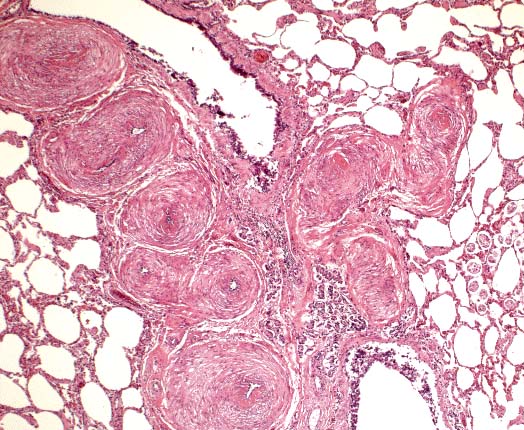

Neuronal vacuolation in the brain stem of a Suffolk ewe with scrapie. (HE, 100X, 61K)

Contributor's Diagnosis and Comments: Brain stem: The sections of brain stem and spinal cord display cytoplasmic neuronal vacuolation.

AFIP Diagnosis: Brain stem: Neuronal vacuolation, multifocal, with mild astrocytosis, and multifocal axonal degeneration, Suffolk, ovine.

Conference Note: Scrapie is a disease with international scope and implications. It is a chronic disease involving the central nervous system of sheep and goats and has an incubation period of 1.5 to 5 years, depending on the age at exposure. Infection usually occurs around the time of birth, and probably via ingestion, but the possibility of vertical modes of transmission remains. The agent initially proliferates within the lymphoid tissues and lower intestine and may take up to 2 years to reach the central nervous system. A further 2 years may elapse before clinical symptoms appear. Early in the disease, animals are alert but excitable, and may have seizures. Later, paresthesia may develop, manifested as agitated rubbing against posts and trees and nibbling at feet and legs. There is progressive dysmetria, emaciation, and finally paralysis and death. Apart from self-trauma, there are no gross lesions, and no inflammatory changes. Histologically, the most characteristic finding is the presence of intraneuronal vacuoles in the CNS.